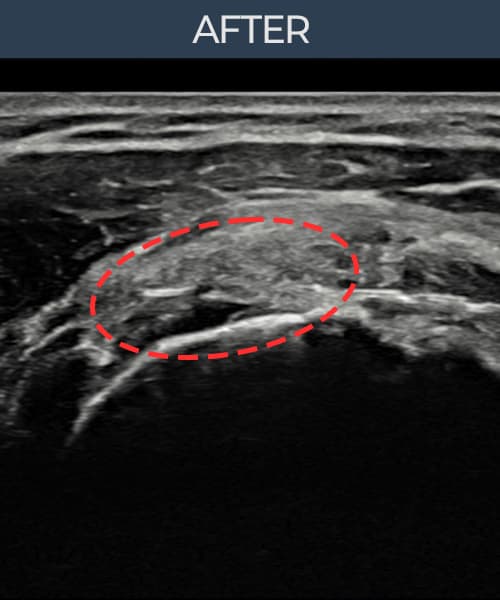

超音波検査にて腱板 関節面側部分断裂(14mm × 7mm (腱厚の約68%欠損))を確認。縫縮術施行後、腱の連続性が回復し、日常生活に復帰されました。

施術後

術前超音波にて腱板 関節面側部分断裂・肩棘上筋腱のエコー不連続と腱欠損(14mm × 7mm (腱厚の約68%欠損))を確認。術後超音波では断裂部位が再生組織で充填され、腱の連続性回復とエコーパターンの正常化が確認されました。

持続する肩痛で来院された患者様です。超音波検査にて腱板 関節面側部分断裂(欠損:14mm × 7mm (腱厚の約68%欠損))を確認し、超音波ガイド下で非手術的縫縮術を施行しました。術後は約4〜6週間のブレース装着の後、段階的なリハビリプログラムを実施。経過超音波で腱の連続性回復を確認し、患者様は無事に日常生活へ復帰されました。